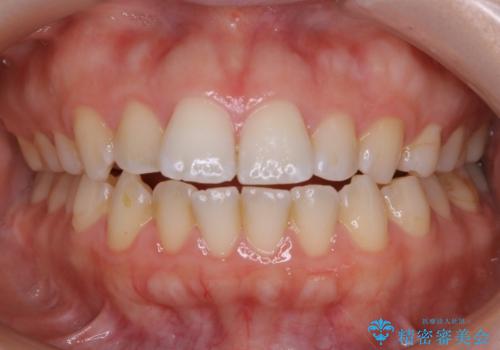

- 歯のガタつきによる見栄えや清掃困難を主訴にご来院されました。

左側の噛み合わせは上の歯が前方に寄ってきてしまっていることが原因のズレがありました。

ガタつき自体は歯列の幅の拡大やディスキング(IPR)でほとんど解消可能でしたが、噛み合わせのズレは歯の移動が必要だったため、左上にマイクロインプラントを使用し噛み合わせの改善とガタつきの解消を同時に進めるという方針をとりました。